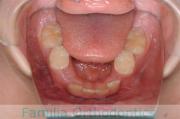

No.14V-516

- 上顎前突

- 叢生

- 10歳

- 女性

- 上:

- 44

- 下:

- 55

- 主な使用装置:

- FEA

- 治療にかかった費用:

- 90万円

きれいな歯並びにしたいということで来院されました。第一期治療で六歳臼歯の位置を維持する装置を入れて第二期治療の準備をしました。第二期は中学生になってから小臼歯を抜歯して行いました。二期治療は約2年半、25回程度の通院が必要でした。